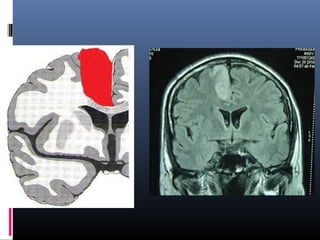

Middle cerebral artery infarction - superior

branch

Clinical features

1.Contralateral hemiplegia – face and

upper limb more involved than

lower limb.

2. Contralateral hemisensory loss.

3.Conjugate gaze paresis(patient looks

towards the side of lesion.

4.Broca’s dysphasia (if left sided)